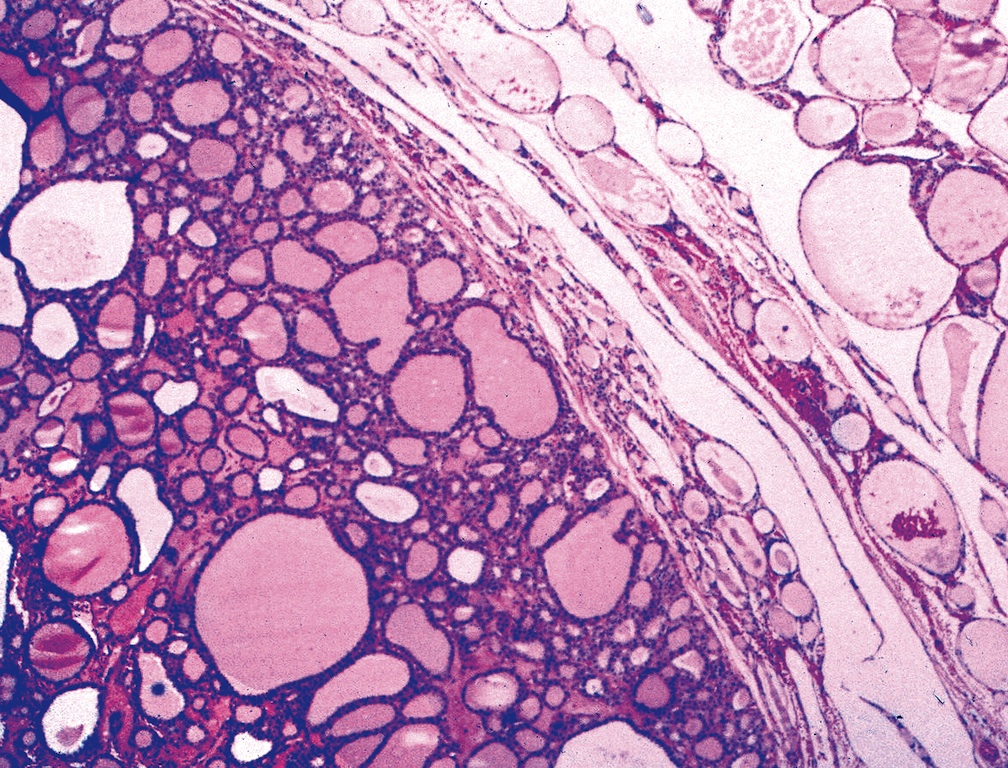

Microscopic (histologic) description

- Architecturally and cytologically different from surrounding gland

- Compression signs in surrounding thyroid tissue

- Encapsulated; thin or moderately thick capsule

- Architectural patterns (can be seen in any combination)

- Macrofollicular (colloid): large follicles, flattened epithelium, abundant colloid

- Secondary changes: fibrosis, hyalinization, hemorrhage, hemosiderin deposition, edema, cystic degeneration, calcification, osseous or cartilaginous metaplasia

- Variants

- Follicular adenoma with papillary hyperplasia: cystically dilated follicles, intraluminal papillae

Microscopic (histologic) images

Contributed by Shipra Agarwal, M.D., Andrey Bychkov, M.D., Ph.D., Mark R. Wick, M.D., Asmaa Gaber Abdou, M.D. and AFIP

Patterns: